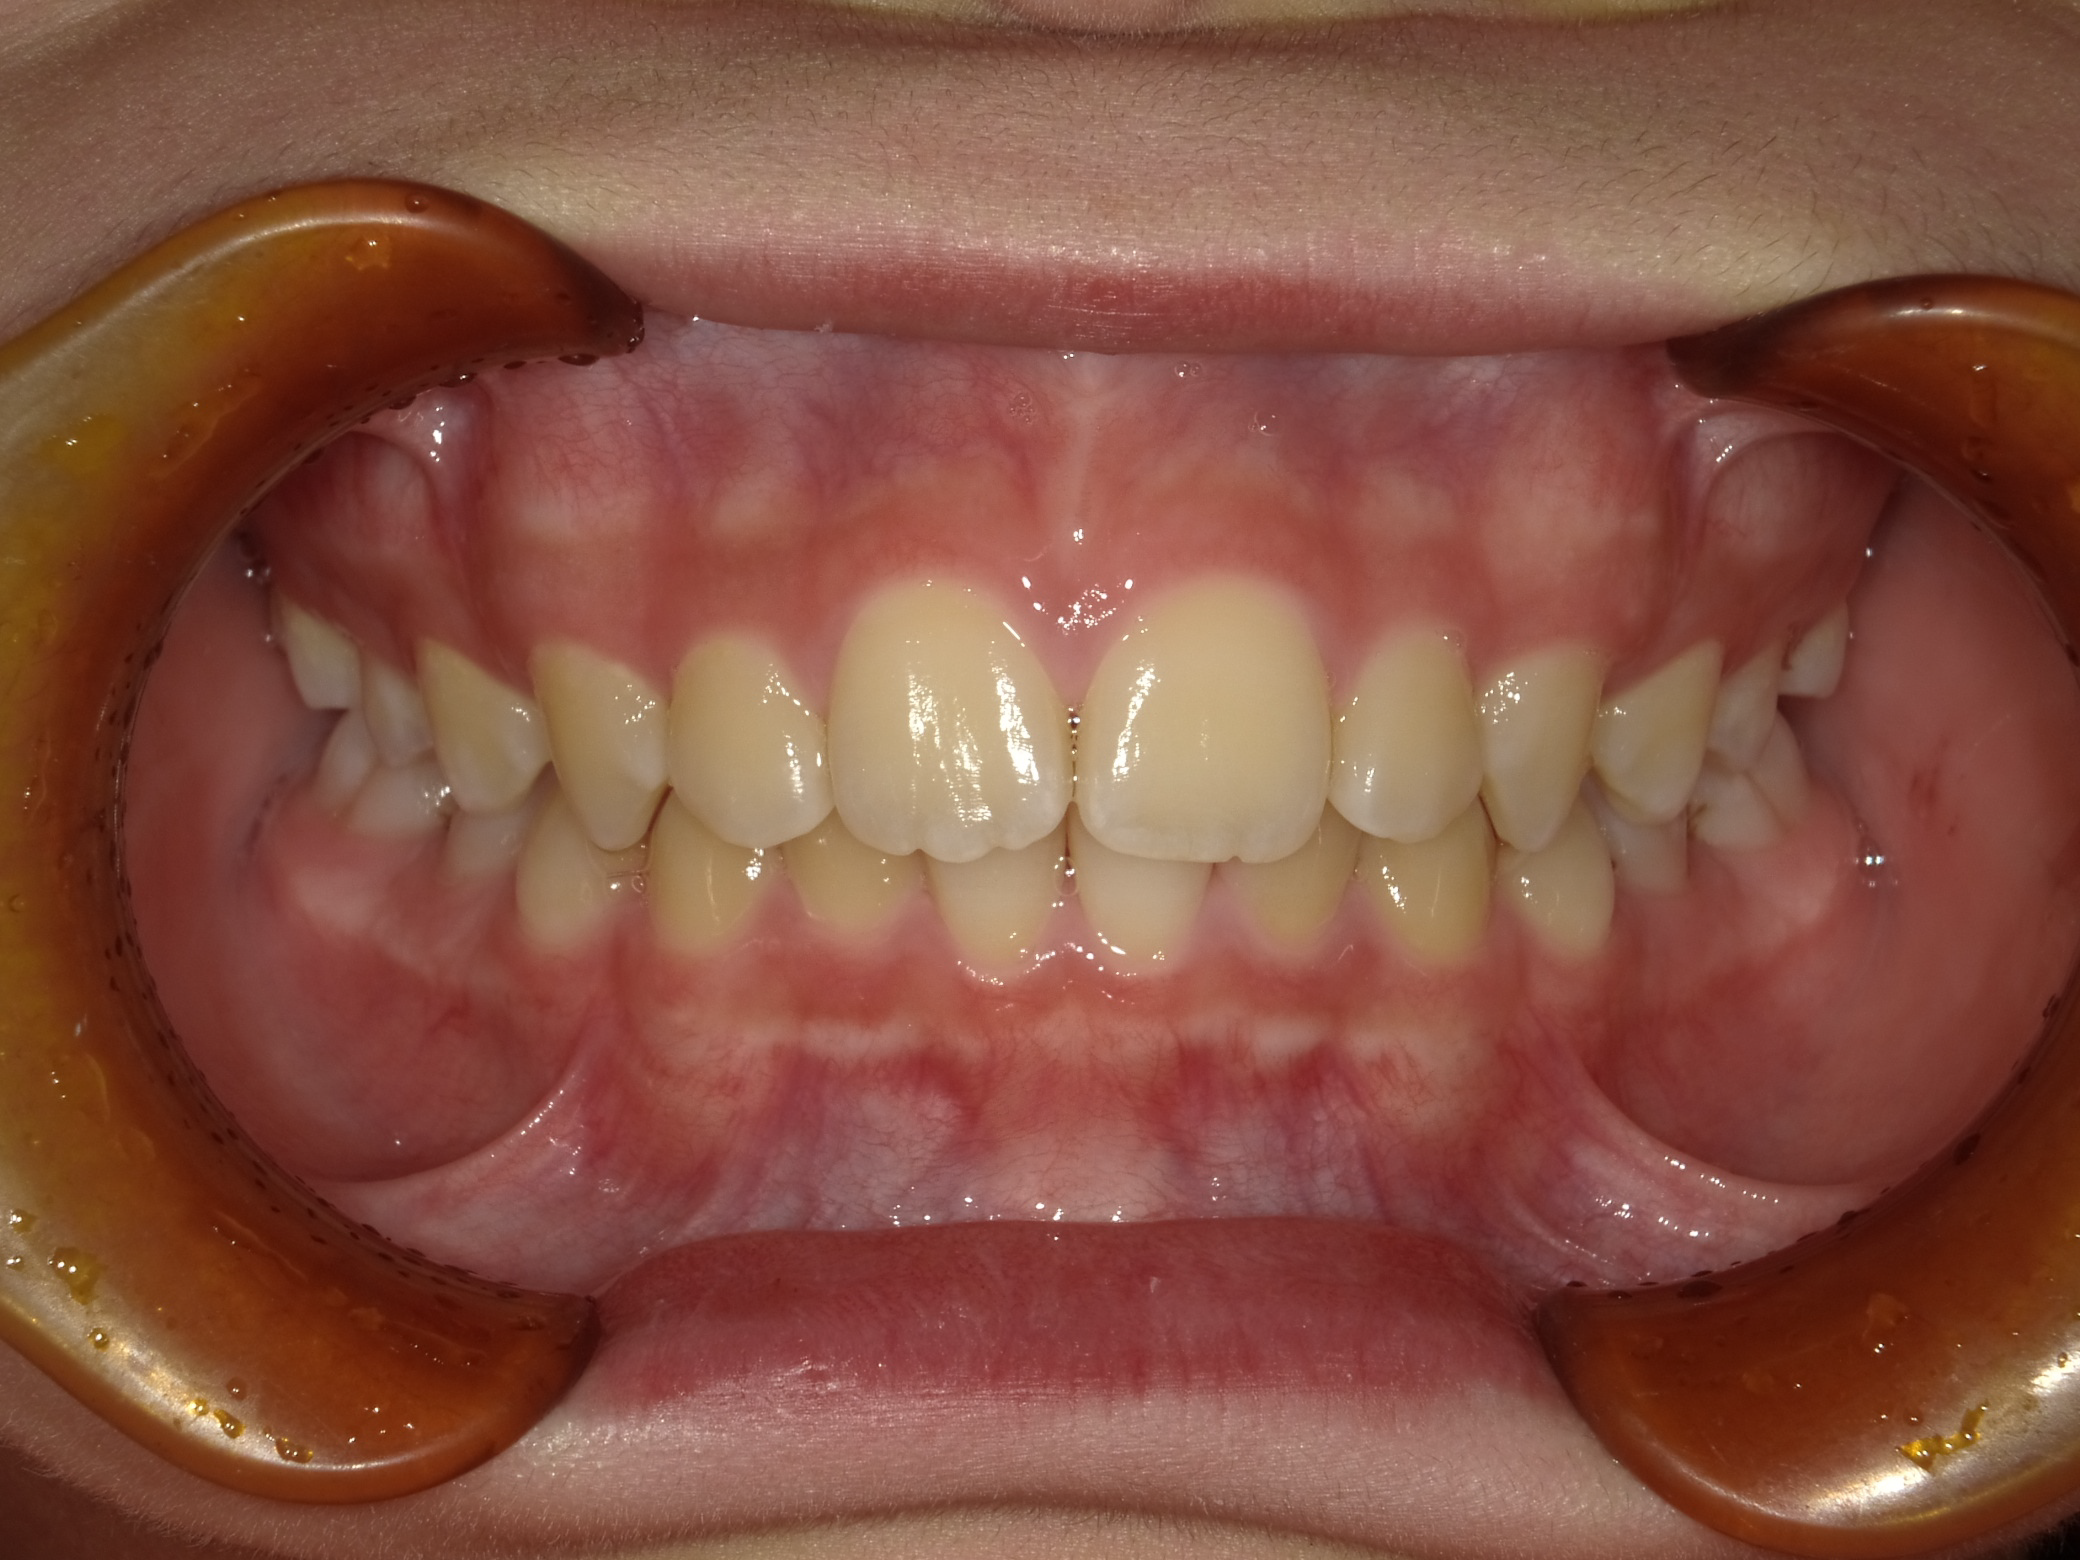

治療前の状態

下の前歯も左右とも内側に生えている歯が並ぶスペースがなく、このままでは凸凹の状態が残ります。

また、横顔を見ても上唇が突出し、上顎前突(いわゆる出っ歯)の状態です。上の歯が下の歯を全て覆い前から見ても下の歯が見えません。

このままでは、将来的に奥歯の負担が大きくなり、歯を失う原因になる可能性があります。叢生(凸凹)の改善と、上顎前突の改善を目的に1期矯正を開始しました。